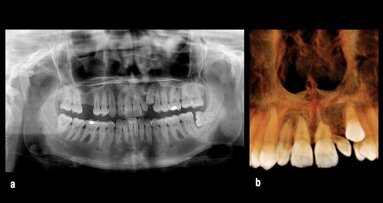

Desplazamiento de disco sin reducción con limitación de apertura bucal

Los trastornos temporomandibulares (TTM) son condiciones musculoesqueléticas ...